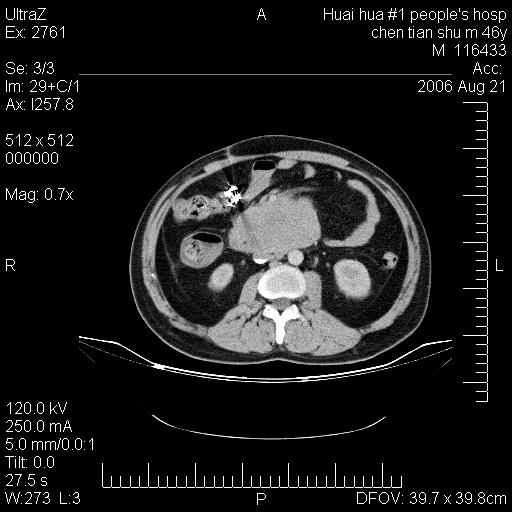

患者,男,46y。腹痛2月,消瘦。

十二指肠水平段占位,考虑间质瘤或平滑肌瘤。

肿块较大,腹膜后占位,境界欠清,周边脂肪密度较高呈条状影,有没有脂肪肉瘤可能,

缺少完整的三期图像。考虑肠系膜脂膜炎mp(肿块型)。

鉴别:间质瘤(这么大而无囊变不可思议)、平滑肌瘤/肉瘤、淋巴瘤、类癌,脂肪类肿瘤、转移瘤等。

十二指肠水平段占位,考虑间质瘤。

首先考虑小肠间质瘤。

十二指肠水平段软组织密度占位,考虑间质瘤可能性大。

腹膜后占位,境界欠清,考虑来源于十二指肠病变,间质瘤或平滑肌肉瘤可能性大。建议活检。

手术病理结果:原发性小肠恶性淋巴瘤(primary gastrointestinal lymphoma,pgil)是原发于胃肠的淋巴网织系统的恶性肿瘤,在结外淋巴瘤中居第一位,该病少见,临床无特异性,诊断困难,术前主要依靠影像学诊断。胃肠道本身具有较丰富的淋巴组织,因而胃肠原发性淋巴瘤是结外淋巴瘤最常见的部位,文献报道约占胃肠道恶性肿瘤的1%~4%,其中胃约占50%~70%,小肠约占35%~70%,结肠约占4%~6%。影像检查在pgil的诊断及分期中有重要的作用,ct是很有价值的检查方法。

胃肠淋巴瘤病理特点:胃肠道原发性淋巴瘤起源于胃肠壁固有层和黏膜下层的淋巴组织即胃肠粘膜相关淋巴组织(malt),多为粘膜相关淋巴瘤。病理上通常为非霍奇金淋巴瘤,且决大多数来源于b淋巴细胞,很少见于霍奇金淋巴瘤。胃肠原发淋巴瘤比胃肠道癌的发病率要低的多,最常见于胃,其病因可能跟幽门螺杆菌感染有关。幽门螺杆菌能引起胃粘膜损害,引起炎性及免疫反应,淋巴细胞聚集并形成滤泡,可影响胃的正常生理功能,导致胃淋巴瘤的发生。单纯性小肠淋巴瘤是常见好发于回盲末端,受累的肠段较长,可单发、多发,甚至累及整个小肠。原发性大肠淋巴瘤罕见,以直肠和盲肠最多见。病变大体观可表现为胃肠腔内外的肿块,也可表现为从黏膜下到浆膜面肠壁的纵向浸润,并且常常伴有肠系膜淋巴结肿大。任何情况下,肿瘤几乎总是导致一定程度的肠壁增厚,可对称或不对称,病变与正常组织间常无明确分界,肠腔可狭窄、正常或动脉瘤样扩张,后者主要是肿瘤在肠壁内浸润,破坏肠壁内植物神经丛所致。以上改变成为ct检测病变的病理基础。

肠道淋巴瘤的ct表现分为4类

1) 壁内浸润型, (2)多发结节型, (3)肠系膜受累伴腔外肿块型(本型就是),(4)肿块型。